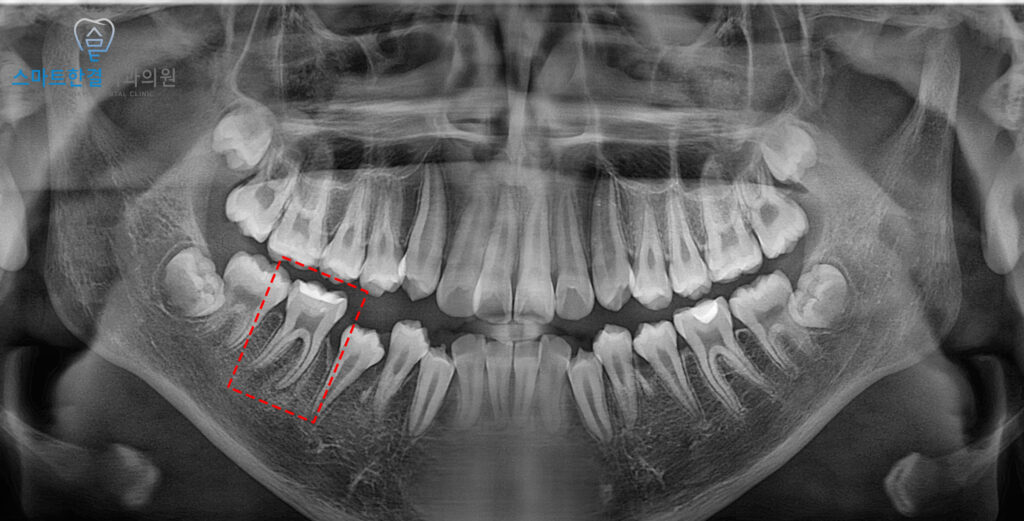

위 환자분께서는 14세 남아로,

오른쪽 아래 안쪽 잇몸에 부기가 발생하여

본원에 내원해 주셨는데요.

환자 보호자분께서는

예전에 다른 병원에서 해당 치아의

충치를 제거하는 과정 중 신경이 노출되어,

노출된 신경 위에 보호제를 덮어

자극을 방지하는 치료를 받았다고 하셨어요.

그 이후 비가역성 치수염으로

발전한 것으로 추정되었는데요.

본원에서는 처음 내원 시,

절개 및 배농을 시행하여

염증을 제거한 후

증상이 해소되었어요.